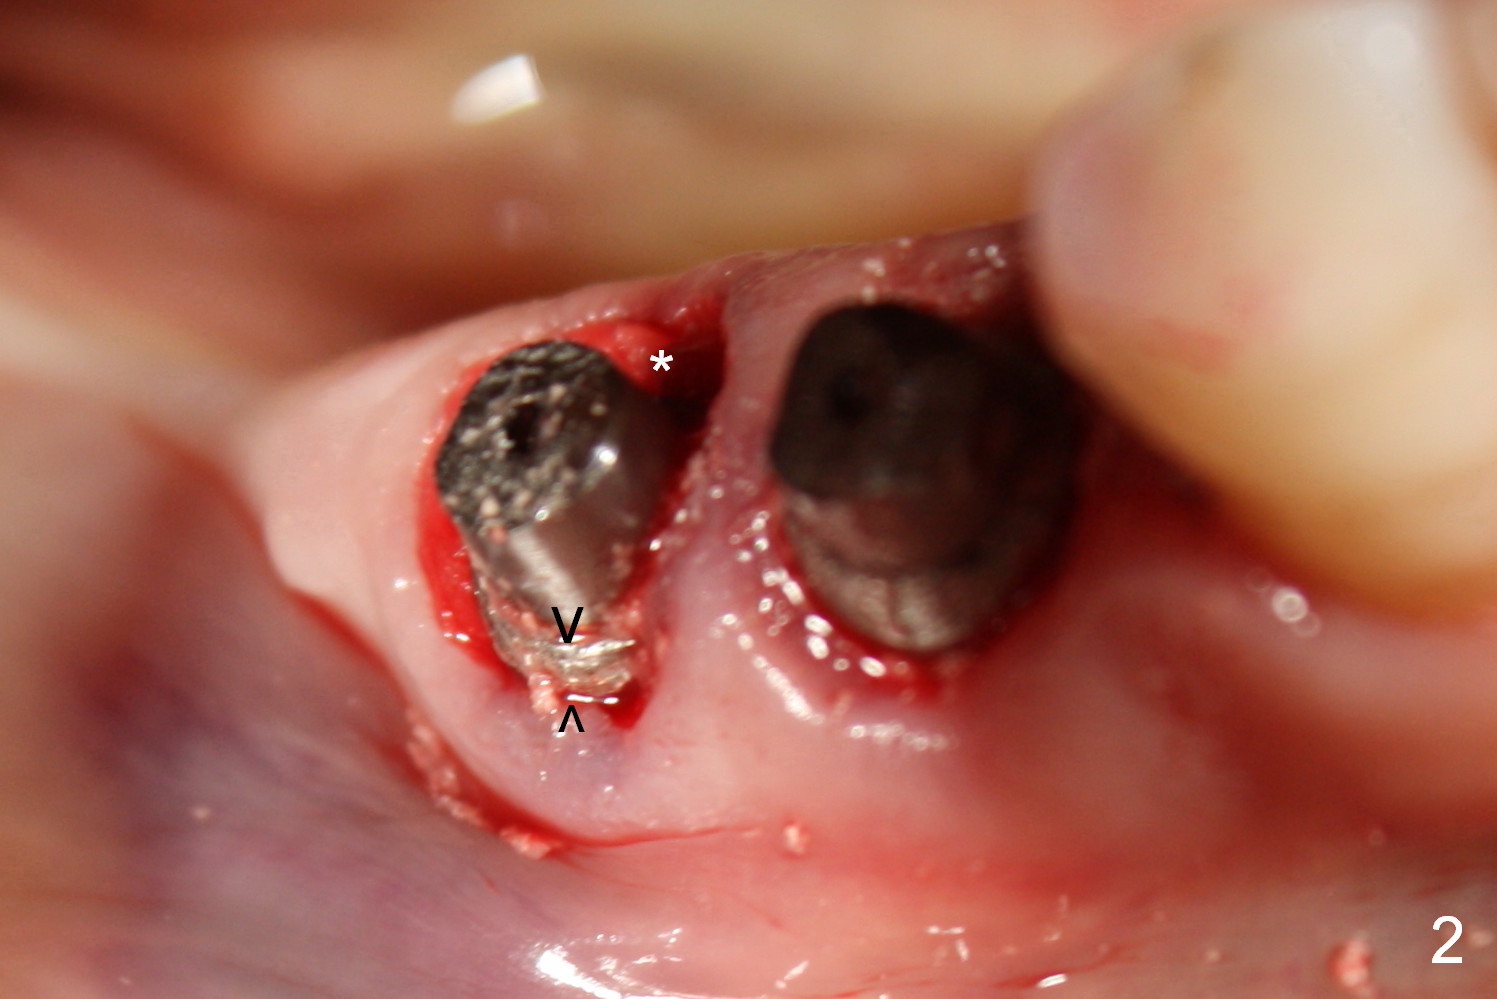

Fig.1 shows preop condition, whereas Fig.2 immediately post placement. In fact there is a space lingual to the implant of #29 (*). At that moment, the buccal margin is within normal limit (arrowheads). Ideally, the malpositioning can be corrected immediately. The implant should have been removed, repositioned and placed at the right position and trajectory. It is possible that attention was being paid to the depth of the osteotomies, because of proximity to the Mental Loop.

Four months and a half, the buccal margin has to be extended (Fig.3 ^). A month later, gingival recession becomes more obvious (Fig.4 ^ with exposure of the rough surface of the implant). Occlusal view demonstrates the buccal position of the implant and abutment at #29 (Fig.5). CBCT will be taken to confirm the malpositioning. If it is confirmed, the abutment and implant will be removed and un-torqued. The lingual bone will be removed; osteotomy will be also extended apically cautiously. The same or longer implant will be placed immediately. Probably two 1 piece implants will be placed at the same time at the site of #30, since the ridge is narrow.